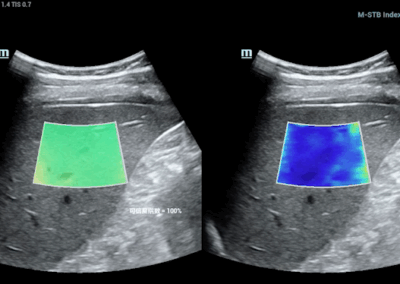

RESONA i9

Resona I9 es un sistema de ecografía de aplicación general con características notablemente innovadoras. Estas innovaciones se desarrollan sobre la base de conocimientos profundos en situaciones clínicas complejas, para proporcionar respuestas precisas y oportunas, una gran eficiencia y una notable experiencia de usuario.

Se puede ajustar para utlizar mejor el espacio

Satisface fácilmente las distintas necesidades de exploración

- Diseño del panel de control inteligente y específico para exámenes clínicos con teclas especiales de tinta electrónica

- Diseño innovador y adaptable para diferentes situaciones clínicas